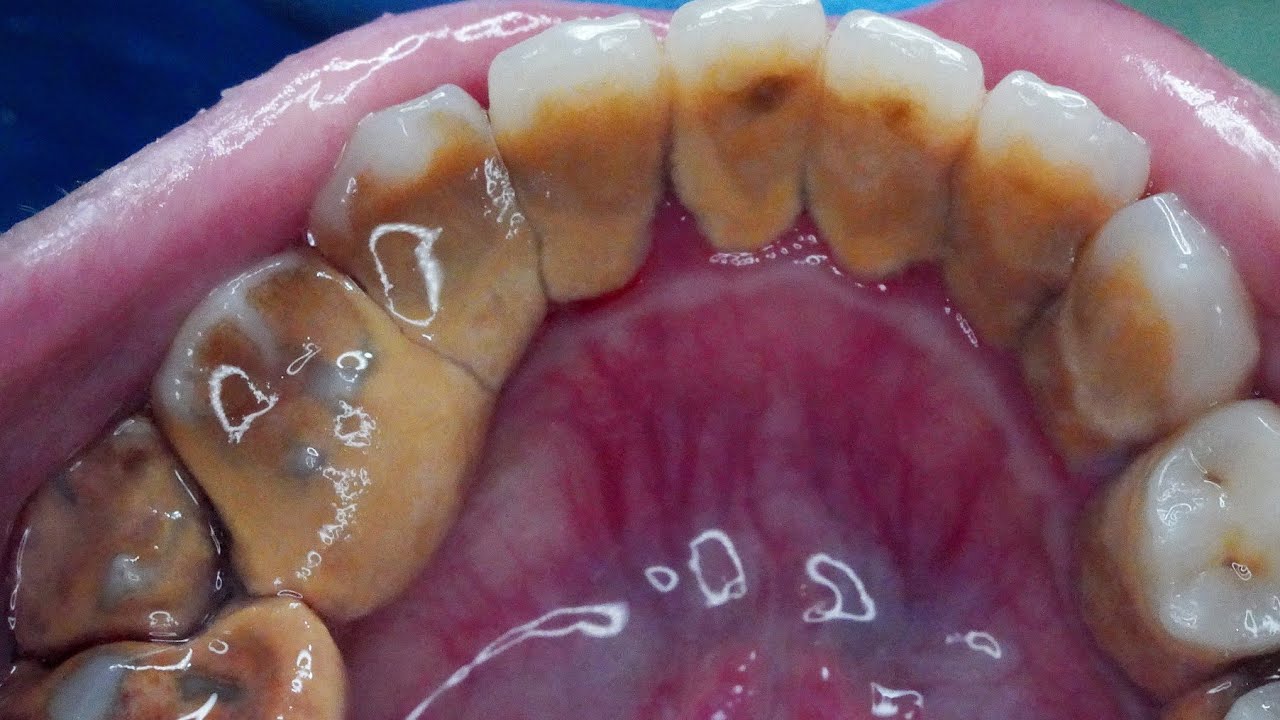

풋케어, 피지압출, 귀청소, 치석제거 등